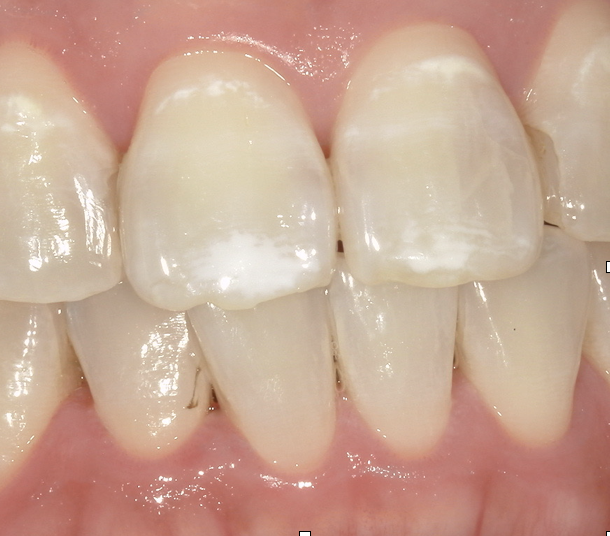

歯の表面に時々みられる下の写真のような白い斑点のことをホワイトスポットと言います。

🔼Before